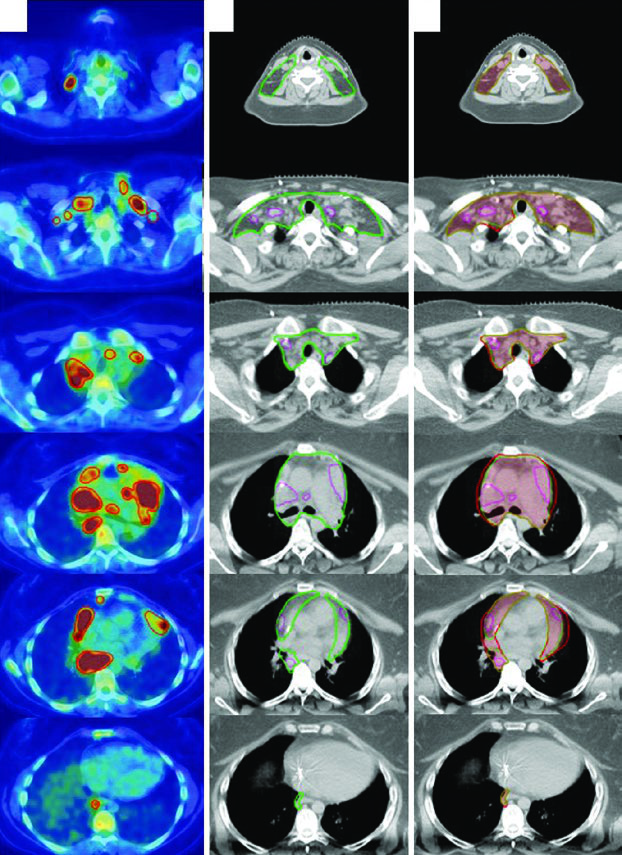

Axial slices of pre-chemotherapy PET-CT and post-chemotherapy simulation CT showing ISRT delineation for stage IIA Hodgkin lymphoma involving left supraclavicular and mediastinal regions

Figure 31.1 — Stage IIA HL: pre-chemo GTV (red) and ISRT CTV (green) on simulation CT. Source: Target Volume Delineation and Field Setup, 2nd Edition

ISRT emerged over the past decade from ongoing efforts to minimize late treatment effects and improve quality of life for survivors. When patients are seen by the radiation oncologist prior to diagnostic imaging, involved-node radiation therapy (INRT) can be employed. INRT and ISRT share similar delineation principles, but ISRT margins must be larger to account for uncertainties in contouring the CTV when optimal pre-treatment imaging is unavailable.

INRT is the common approach in Europe where a pre-chemotherapy PET-CT in treatment position is routine. In North America, where such imaging often is not available in the radiation therapy position, ISRT remains standard practice. For a comprehensive overview of delineation approaches across all disease sites, see our complete guide to target volume delineation.

A 27-year-old male with stage IIA, non-bulky, favorable-risk nodular sclerosing HL involving the left supraclavicular and mediastinal nodes received 2 cycles of ABVD. Post-chemotherapy PET showed complete metabolic response (Deauville 2). Per German Hodgkin Study Group H10 criteria, he received 20 Gy of consolidation RT.

The pre-chemotherapy PET/CT was registered to the simulation CT. Changes in arm positioning, hyperextended neck, and five-point mask retracting shoulders create anatomic differences between scans — precisely the uncertainties that the ISRT approach accounts for. This patient used a breath-hold technique, so no CTV-to-ITV expansion was needed.

Advanced-Stage Bulky Hodgkin Lymphoma

A 31-year-old woman with stage IIB bulky nodular sclerosing HL involving cervical, supraclavicular, mediastinal, and bilateral hilar nodes received 2 cycles of ABVD (complete metabolic response, Deauville 2 on interim PET) followed by 4 cycles of AVD (Bleomycin dropped for pulmonary toxicity). Consolidation RT was indicated due to initial bulky disease.

The final ITV was derived from 4D-CT at simulation, capturing respiratory anatomic variation. Treatment was prescribed to the ITV plus institutional PTV margin. This case illustrates how ISRT adapts to post-chemotherapy anatomy: the CTV respects the craniocaudal extent of the pre-chemo GTV while limiting radial exposure of adjacent normal structures.